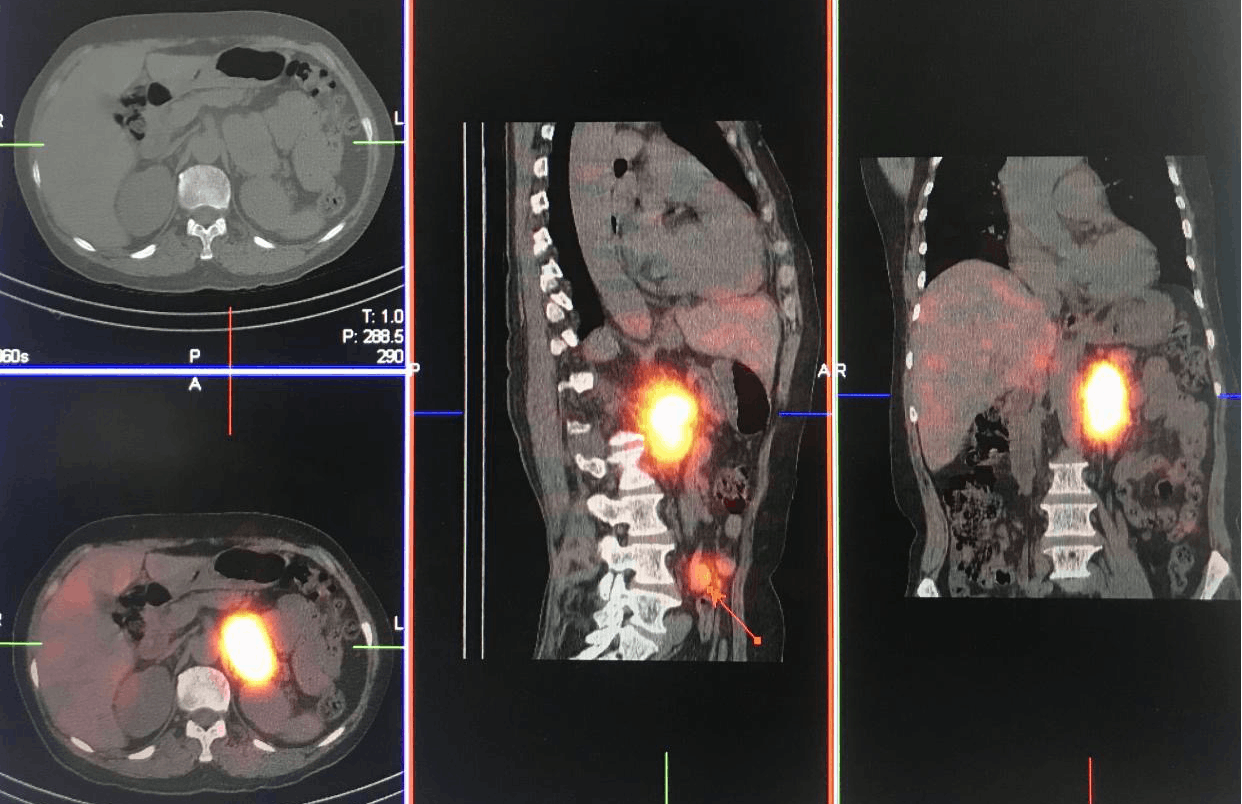

本图为131I-MIBG SPECT-CT显像,左侧肾上腺肿块伴腹膜后淋巴结肿大,特异性摄取131I-MIBG 异常增高,考虑恶性嗜铬细胞瘤并腹膜后淋巴结转移